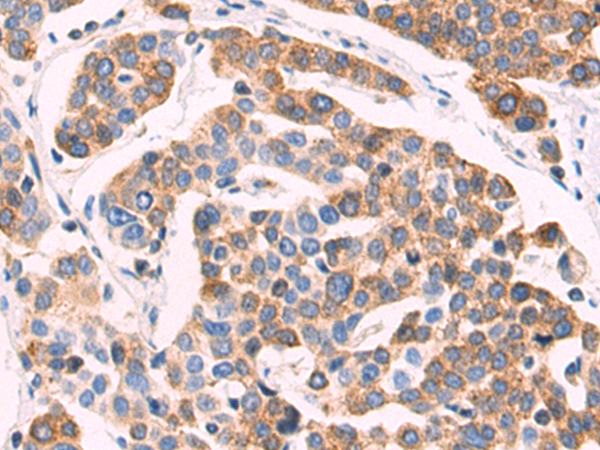

分类: 科研抗体货号: P02533别名:应用: WB,IHC反应种属: Human, Mouse, Rat